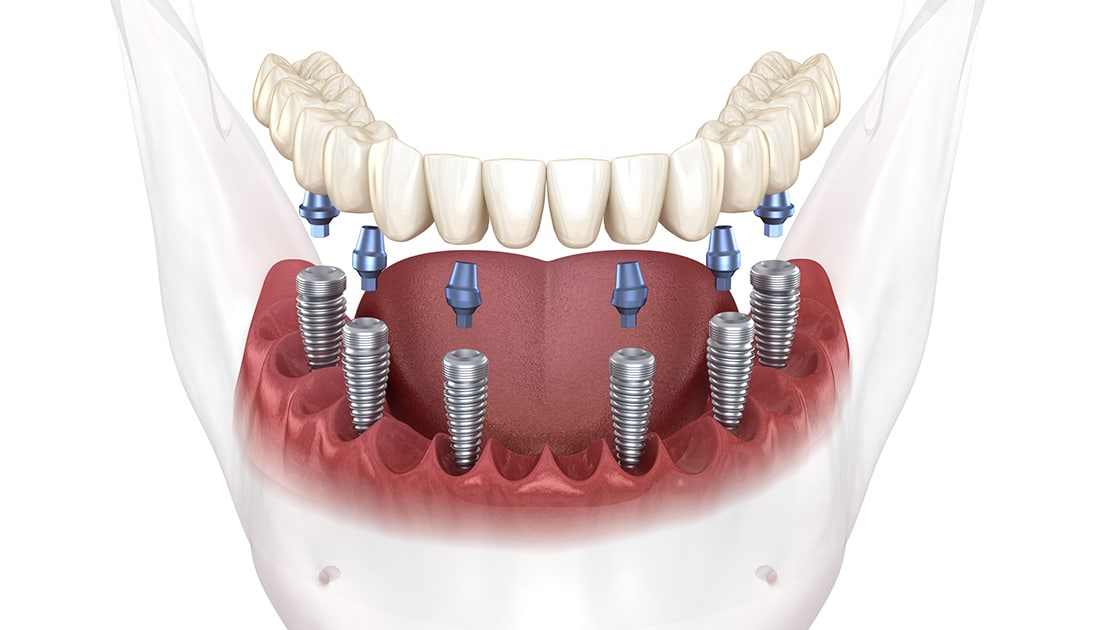

Single Dental Implant

Dental implants are small anchors made of a biocompatible metal called titanium that are placed in the jawbone to replace missing teeth in the mouth. After placement, the anchors will begin to fuse with the bone over the course of a few months. After the fusing process, known as osseointegration, abutment posts are inserted into the anchors to allow for the permanent attachment of the replacement teeth.